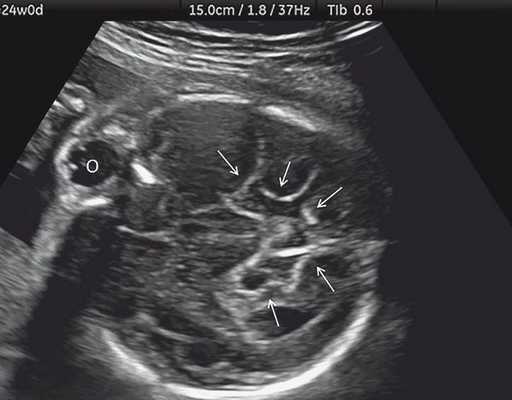

а) Ультразвуковая трехмерная реконструкция (СМ - средний мозг, О - орбита, Ч - червь, М - мозжечок). На плане А показан нижнеаксиальный срез на уровне среднего мозга и орбит, показывающий аномальную бороздчатость медиальной поверхности височных долей (стрелки). Уровень получения этого среза отражен пунктирной линией на плане С. На плане B показан коронарный мозжечковый срез, на котором также отражены выпуклые извилины медиальной поверхности височных долей (стрелки). Пунктирная линия на плане А показывает уровень получения коронарного среза.

б) Нижнеаксиальный ультразвуковой 2D-срез. Уровень среза проходит через средний мозг и орбиты. Стрелки показывают аномально выпуклые извилины медиальной поверхности височных долей (О - орбита)

Основные ультразвуковые характеристики плодов, полученные при нашем исследовании, отображены в таблице 1 и на рис. 1-4.

| Срок беременности | Голова | Грудная клетка | Конечности | Дополнительные находки |

|---|---|---|---|---|

| Набл. 1. 24,3 нед. | БПР - 25,3 нед. ОГ - 24,6 нед. Аномально повышенная бороздчатость и выпуклость извилин нижнемедиальной поверхности височных долей (рис. 1а). | Торакоабдоминальное соотношение - 66,7% (рис. 1б) Длина ребра - среднее для 16 нед. | Бедренная кость 19,6 мм (47,8% от должной), изогнута ("телефонная трубка") (рис. 1в). Остальные кости - среднее для 15 нед. | Уплощенные тела поясничных позвонков. |

| Набл. 2. 20,3 нед. | БПР - 21,5 нед. ОГ - 20,3 нед. Уплощенный затылок. Выпуклые темпоральные бугры (рис. 2а). Аномально повышенная бороздчатость и выпуклость извилин нижнемедиальной поверхности височных долей (рис. 2б). | Торакоабдоминальное соотношение - 63,3% (рис. 2в) Окружность груди - среднее для 18 нед. Длина ребра - среднее для 15 нед. | Бедренная кость 17,7% (61% от должной), изогнута ("телефонная трубка") (рис. 2г). Остальные кости - среднее для 13-14 нед. | Гипоплазия костей носа. |

| Набл. 3. 24 нед. | БПР - 30 нед. ОГ - 27,2 нед. Уплощенный затылок. Выпуклые темпоральные бугры (рис. 3а). Аномально повышенная бороздчатость и выпуклость извилин нижнемедиальной поверхности височных долей (рис. 3б). | Торакоабдоминальное соотношение - 56,6% (рис. 3в) Окружность груди - среднее для 20 нед. Сердце/грудь (см 2 ) - индекс 0,6. | Бедренная кость 23,1 мм (57% от должной), изогнута ("телефонная трубка") (рис. 3г) Остальные кости - 50% для 15-16 нед. Нормальная установка пальцев кисти (рис. 3д). | Многоводие. |

| Набл. 4. 26,5 нед? | БПР - 22,6 нед. ОГ - 22,6 нед. Форма - трилистник (рис. 4а). Боковые желудочки - 22 мм, высокий лоб, расширенный родничок, сагиттальный шов (рис. 4б). | Торакоабдоминальное соотношение - 65,7% (рис. 4в). Окружность груди - среднее для 23 нед. Колоколообразная форма. | ДБ - 23 мм (51% от должной). Остальные кости - 50% для 15-17 нед. Нормальная установка пальцев кисти (рис. 4б). | Уплощенные тела поясничных позвонков (рис. 4г). |

Примечание. БПР - бипариетальный размер, ОГ - окружность головы, ДБ - длина бедренной кости.

Длину бедренной кости оценивали по региональным нормативам, а остальные кости - по Ph. Jeanty. Окружность грудной клетки оценивали по U. Chitkara и соавт. [14], длину ребер - по A.Z. Abuhamad [15].

В наблюдениях 1-3 наличие изогнутой бедренной кости (по типу "телефонной трубки") (рис. 1в, 2г, 3г) позволяло предположить наличие ТД I типа. Целе направ ленное исследование головного мозга этих плодов в дополнение к описанным скелетным признакам показало и картину ДВД. Была выявлена аномально повышенная бороздчатость и выпуклость извилин нижнемедиальной поверхности височных долей у плодов в наблюдениях 1-3 (рис. 1а, 2б, 3б). Это позволило установить диагноз ТД I типа.